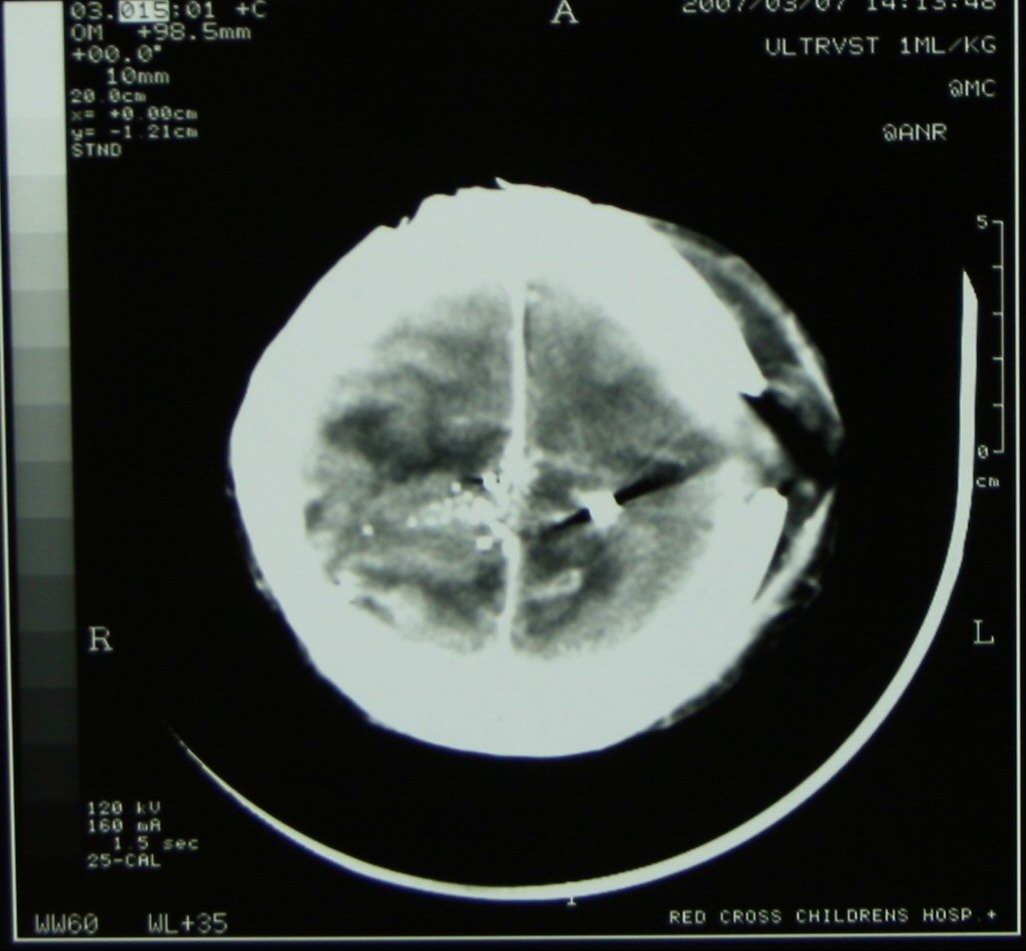

Gunshot fragments in the brain of a 4 year old boy, victim of stray bullets in a township gun battle |